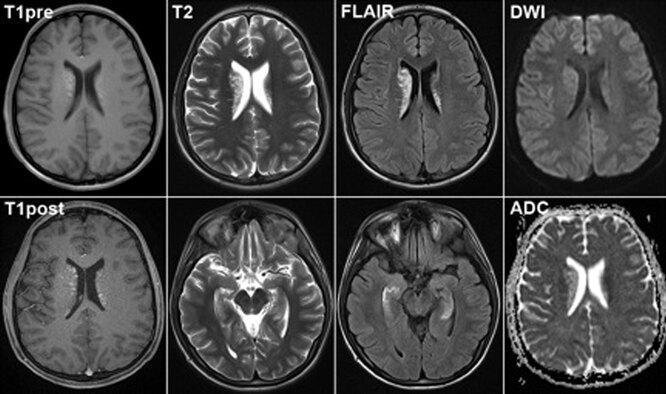

如何证明我们过去认为是三维对象的四维性?托齐和彼得斯建议使用定理在可用的维度中搜索第四维度的某种"阴影"或"回声"博尔苏克-乌兰定理.定理指出,"在任何给定时间,地球上都会有两个截然相反的点,温度相等,压力相等"(当然,除非将地球视为理想的球体)。根据托齐和彼得斯的说法,大脑活动应该产生这样的"对立点":"激活三维大脑S2表面的一个点会导致S3大脑四维表面的两个对立点被激活。相反,激活点 - S3 表面的对立面在三维表面上留下"痕迹",可以通过现有方法来观察大脑活动来捕获。

事实上,文章认为,有一个FMRI将记录两个对立点的同步活动,这将证明我们无法访问的4D现实的存在,我们的大脑居住。